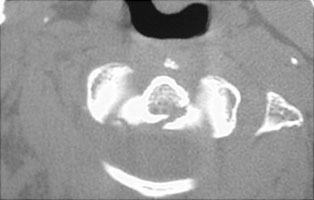

- Click on the image for a larger versionCAxial CT. The fracture at the base of the dens is visible.